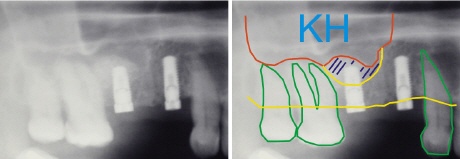

Das Prinzip des einzeitigen Sinus-Lift:

Ein typischer Fall im Oberkiefer Seitenzahngebiet – es ist nicht ausreichend Knochenhöhe vorhanden. Auf der rechten Seite sieht man die relevanten Strukturen des Röntgenbildes durch schematische Linien dargestellt. Die grünen Linien zeigen die Zahnumrisse, dazwischen ist die zu versorgende Lücke.

Die gelbe untere Linie entspricht dem Kieferkamm, der bis zur oberen gelben Linie verläuft. Über dieser oberen gelben Linie beginnt die Kieferhöhle (KH). Der Abstand zwischen den beiden gelben Linien zeigt, wie viel vertikaler Knochen (Knochenhöhe) vorhanden ist. Der rote Pfeil zeigt den unzureichenden Knochenabschnitt.

Durch die spezielle Technik des Sinus-Lifts kann der fehlende Knochen mit dem Einsetzen des Implantats aufgebaut werden. Dazu wir die Kieferhöhlenmembran angehoben (daher die Bezeichnung „Lift“) und des entstehende Raum mit Knochen aufgefüllt. Die rote Linie zeigt schematisch die angehobene Membran, die obere gelbe Linie die alte Position der Membran. Die blau schraffierte Fläche ist der gewonnene Kieferknochenabschnitt um das hintere Implantat herum.